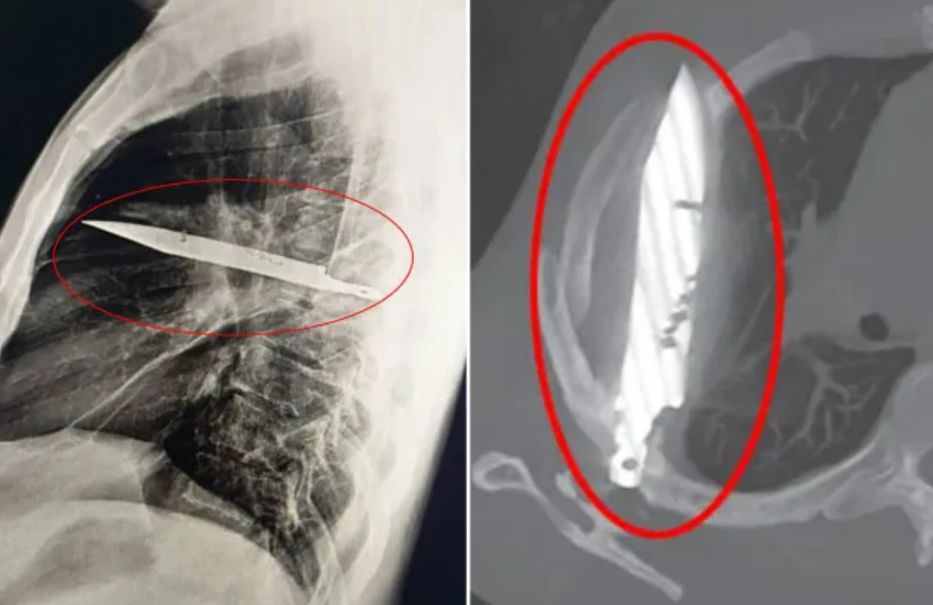

En aquel momento, los médicos suturaron sus heridas y desde ese momento en adelante vivió una vida sin sobresaltos, hasta que su pezón comenzó a supurar pus. Incapaces de determinar a simple vista la causa de la infección, los médicos ordenaron un examen de rayos X y se sorprendieron al ver una enorme hoja de cuchillo alojada en el pecho del hombre.

“Las imágenes iniciales con una radiografía de tórax lateral mostraron un objeto metálico retenido en la parte media del tórax, con opacificación circundante que probablemente representaba un hematoma loculado en resolución o crónico o una fibrosis postraumática, una secuela de la herida de arma blanca del paciente”, escribieron los médicos en su estudio de caso.

De alguna manera, la hoja del cuchillo, que había entrado por el omóplato derecho, esquivó milagrosamente cualquier órgano vital. En el momento del altercado, el hospital donde lo atendieron no tenía medios para realizar un estudio radiológico y, como no reportó dolor después de que sus heridas sanaron, nadie se molestó en investigar más.

Los médicos explicaron que el pus se debía a la acumulación de tejido muerto alrededor del cuerpo extraño, y se maravillaron de que el hombre hubiera vivido ocho años con semejante pieza metálica en el cuerpo sin sentir molestias.

Tras el impactante descubrimiento, la hoja fue extraída cuidadosamente mediante cirugía, junto con el tejido muerto y el pus. El paciente pasó 24 horas en cuidados intensivos antes de ser trasladado a la sala general durante otros diez días. Su recuperación fue satisfactoria y las visitas de seguimiento posteriores transcurrieron sin incidentes.